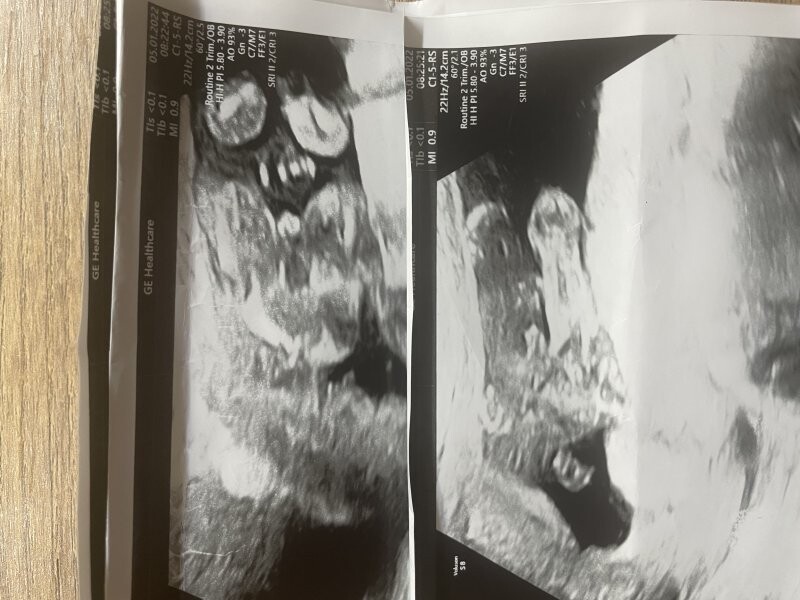

Dobrý den paní doktorko, jsem momentálně těhotná (mám za sebou jedno zamlklé těhotenství, miminko je opravdu vymodlené). První ultrazvuk byl 17.8 (dle ms mělo být 6+3) a pan doktor v CAR vypočítal těhotenství na 6+0 s AS, což není nic zvláštního, protože vzhledem k PCOS mívám ovulaci opravdu později. Vzhledem k tomu, že pracuji v nemocnici a stal se mi tam takový malý úraz (uklouzla jsem) tak se mi hned pan doktor nabídl, že uděláme kontrolní ultrazvuk (tudíž jiný lékař, jiný ultraz.přístroj). Vyděšil mě když těhotenství vypočítal jen na 6+2 místo 7+0 (bylo to po týdnu). Akce srdeční byla stále..jen mám strach, že se opravdu začíná opožďovat ve vývoji a znovu mě potká zamlklé těhotenství. Přikládám foto z obou ultrazvuků. Připadá mi i laickým okem, že embryo rozhodně větší je. Je možné, že to pan doktor špatně změřl? nebo že každý přístroj měří jinak?Děkuji vám !

Dobrý den, teď je otázka, která struktura byla měřená, zda EES (časná délka embrya) - mluvit o CRL je v tomto týdnu brzy.. nebo např. průměr gestačního váčku.. takto se dle fotky momentálně nejeví nic dramaticky špatně, proto bych vyčkala do další kontroly, v těchto nižších týdnech může být ta velikost taková variabilní a nelze pominout i možnost nepřesného měření. Držím palce!